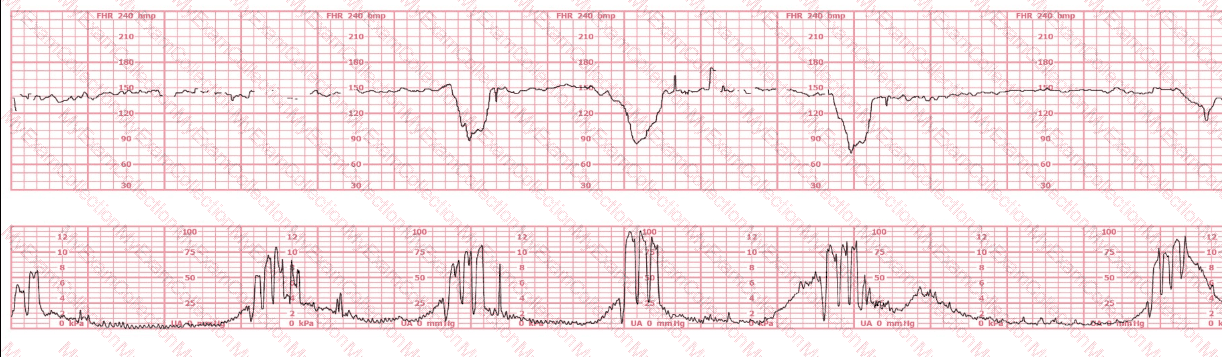

A woman is being induced with oxytocin. The tracing shown is representative of 20 minutes. Based on this tracing, the next step would be to: